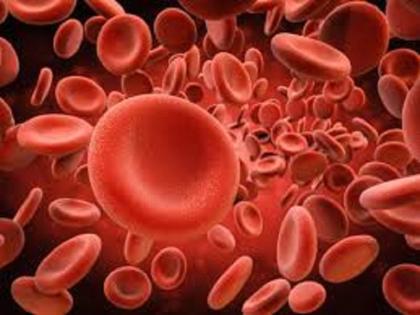

या आजारात लालपेशी जीवंत राहण्याची क्षमता कमी होऊन १० ते २५ दिवसांची होते. त्यामुळे शरीरात रक्ताची कमतरता भासते.

थॅलेसेमिया एक रक्तासंबंधी आजार असून हा आजार अनुवांशिक आहे. एका निरोगी व्यक्तीच्या शरीरातील आरबीसी म्हणजे लाल रक्ताच्या पेशींची संख्या ४० ते ४५ लाख प्रति घन मिलीमीटर असते. थॅलेसेमिया या आजारात आरबीसी नष्ट व्हायला सुरुवात होते. त्यामुळे नवीन पेशी तयार होण्याची प्रक्रीया पूर्णपणे थांबते. साधारणपणे लाल पेशींचे जीवनमान १२० दिवसांचे असते. या आजारात लालपेशी जीवंत राहण्याची क्षमता कमी होऊन १० ते २५ दिवसांची होते. त्यामुळे शरीरात रक्ताची कमतरता भासते.